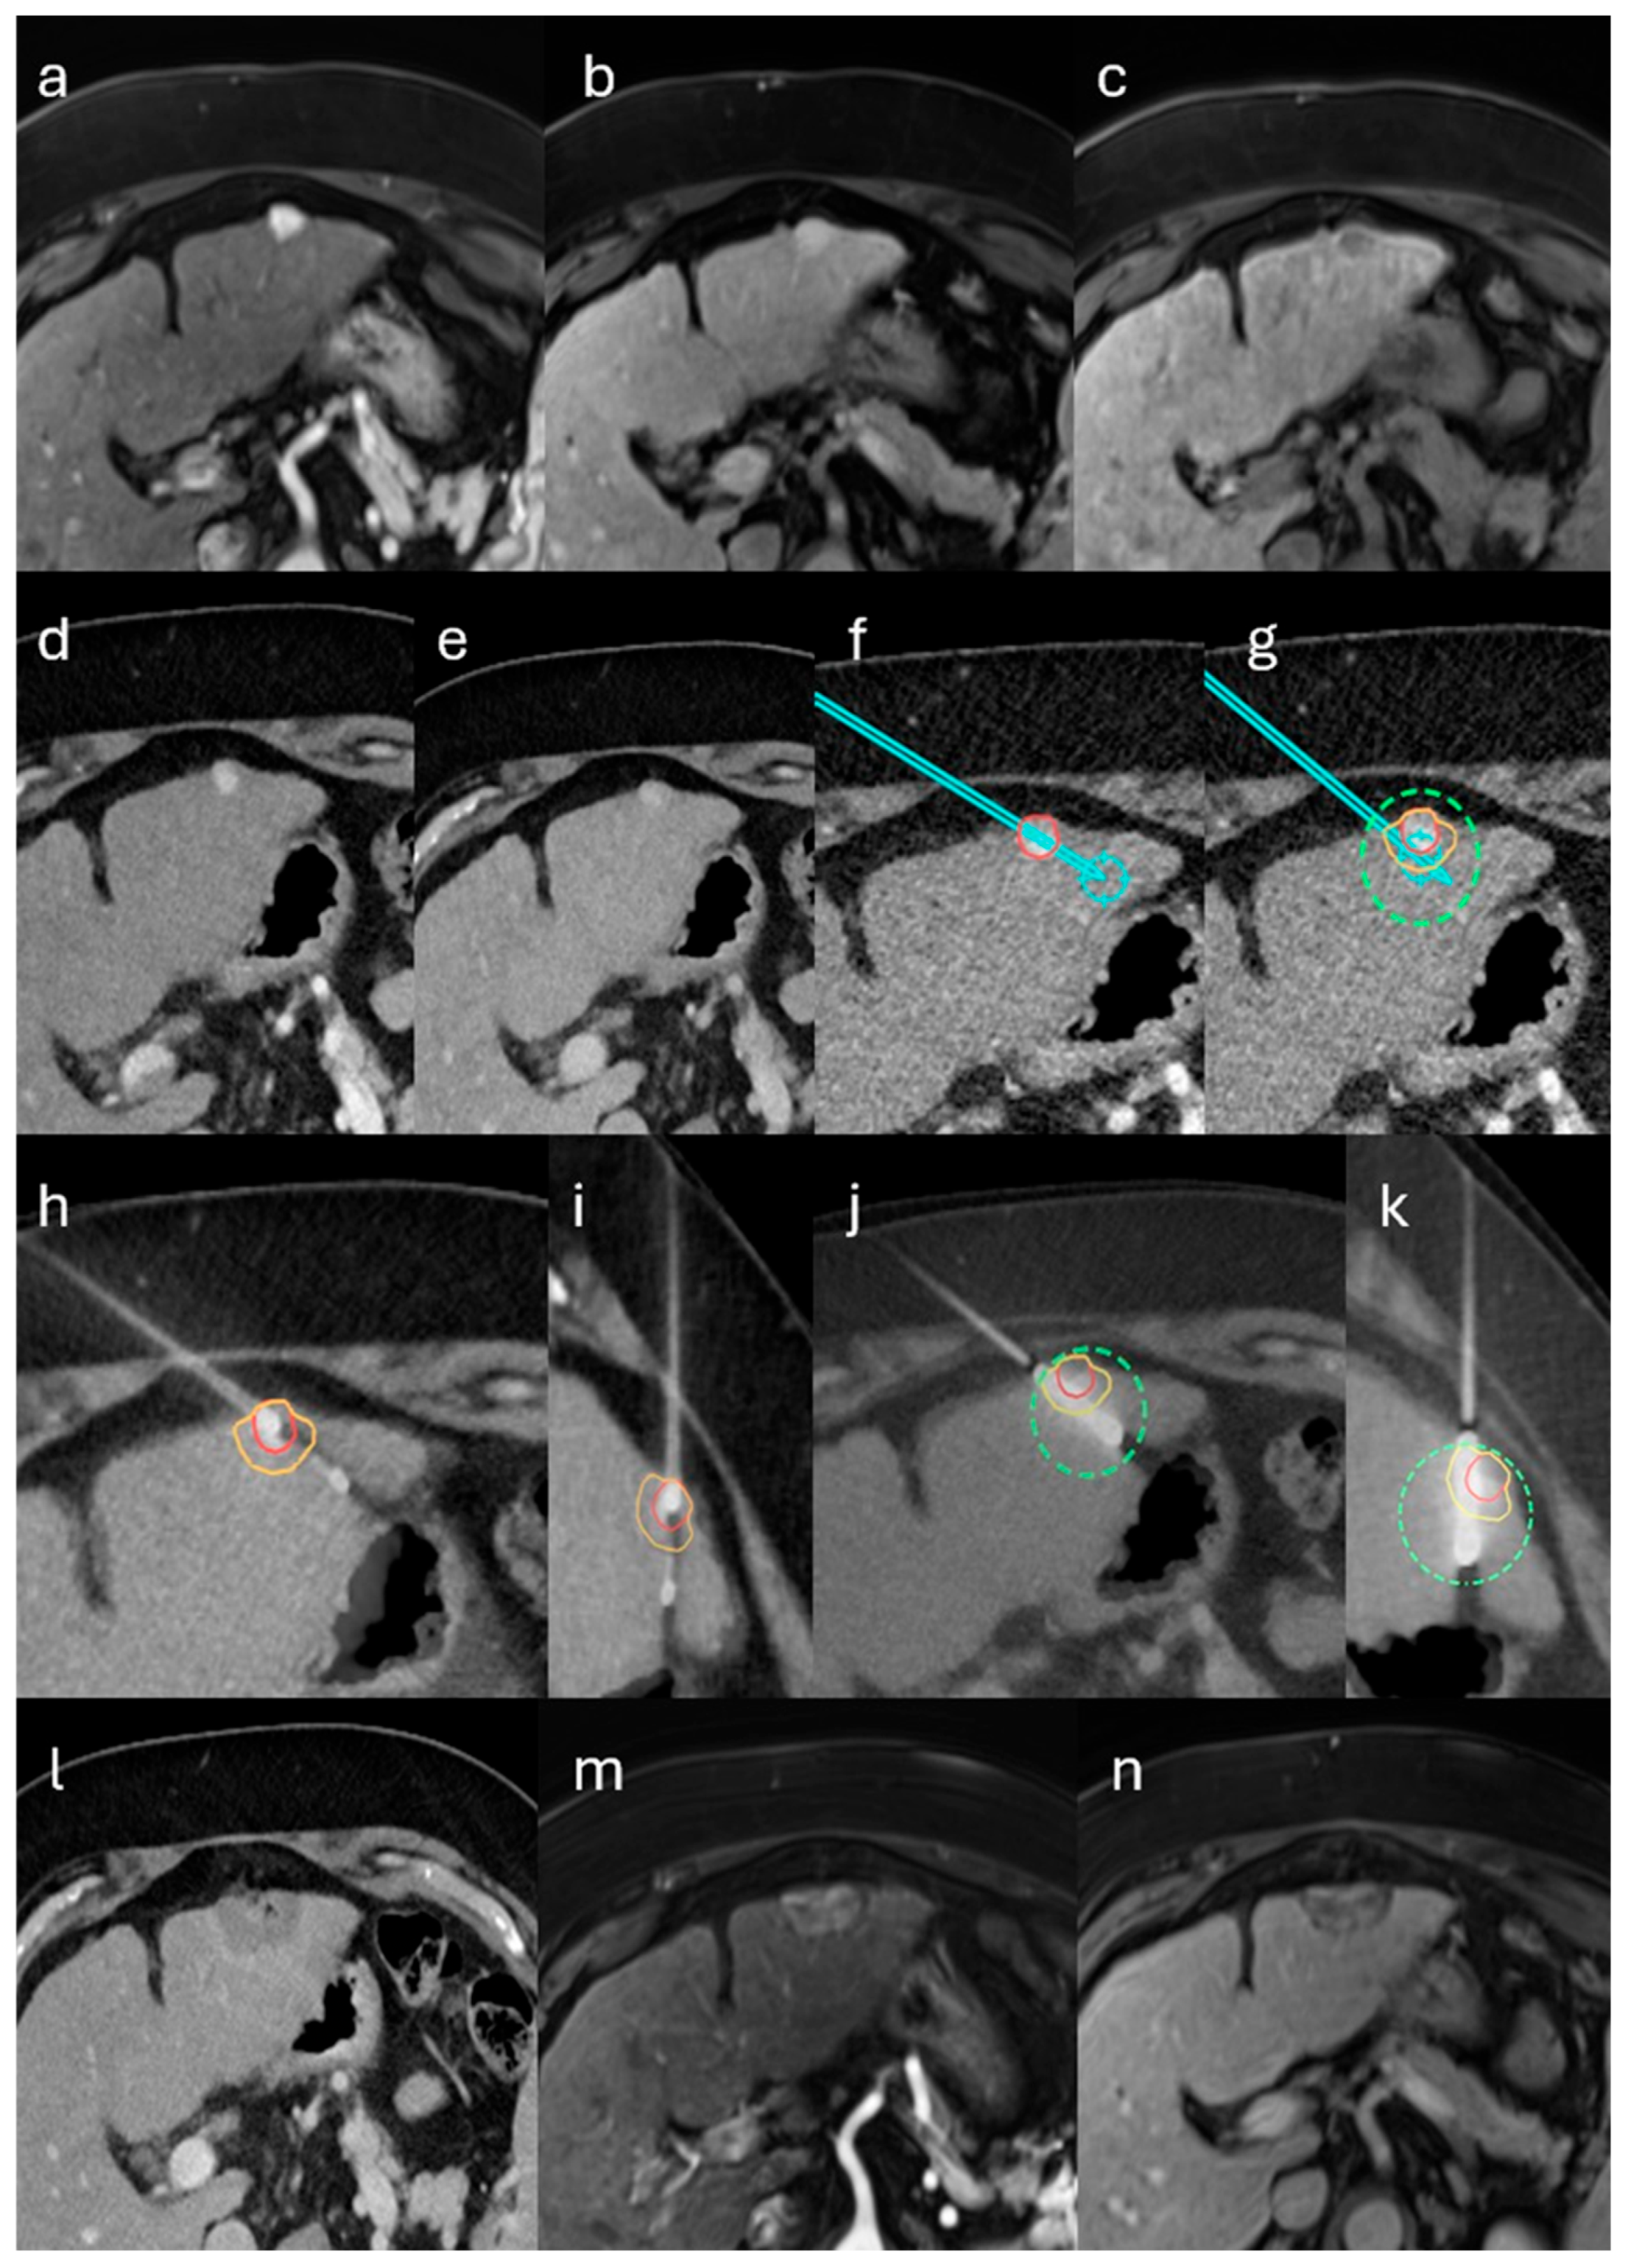

2.2. Stereotactic Biopsy and MWA